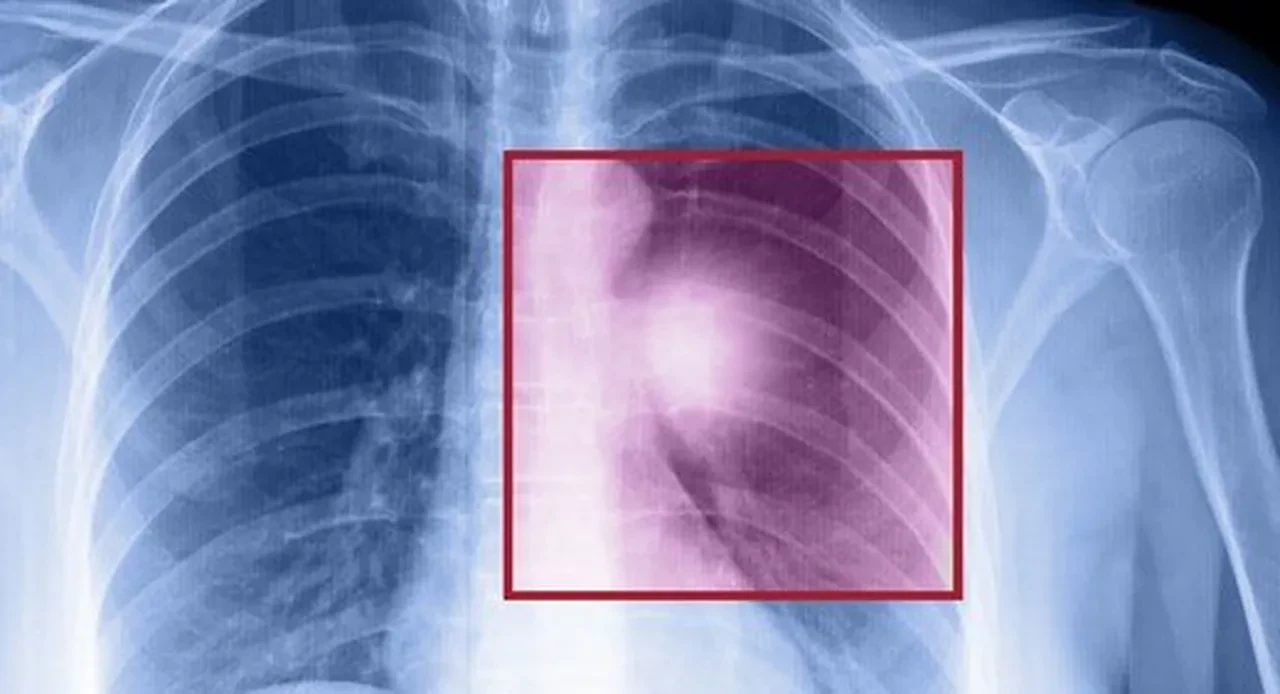

Evinde hayvan besleyen birçok kişiyi tedirgin eden olayın ardından, Okan Diköz’ün yakın akrabası Sakarya Eğitim ve Araştırma Hastanesi Nöroloji Kliniğinden Prof. Dr. Murat Alemdar, kamuoyuna yansıyan olayla ilgili bilgi verdi. Diköz’ün ölümünün, kedi tüyü yutması ile bir ilgisi olmadığını belirten Alemdar, ölüm sebebinin akciğer kanseri olduğunu ifade etti.

Prof. Dr. Murat Alemdar, "‘Kedi tüyü sebebiyle vefat etti’ haberleri, muhtemelen kendisinin çok bilinen hayvanseverliği nedeniyle oluşan yanlış algıya bağlı yapılmıştır. Gerçek ölüm sebebi, akciğerlerindeki kanser tutulumu olup kamuoyunun bu konuda doğru bilgilenmesini isteriz. Ölüm nedeninin kedi tüyü yutmasıyla bir ilgisi yok" dedi.